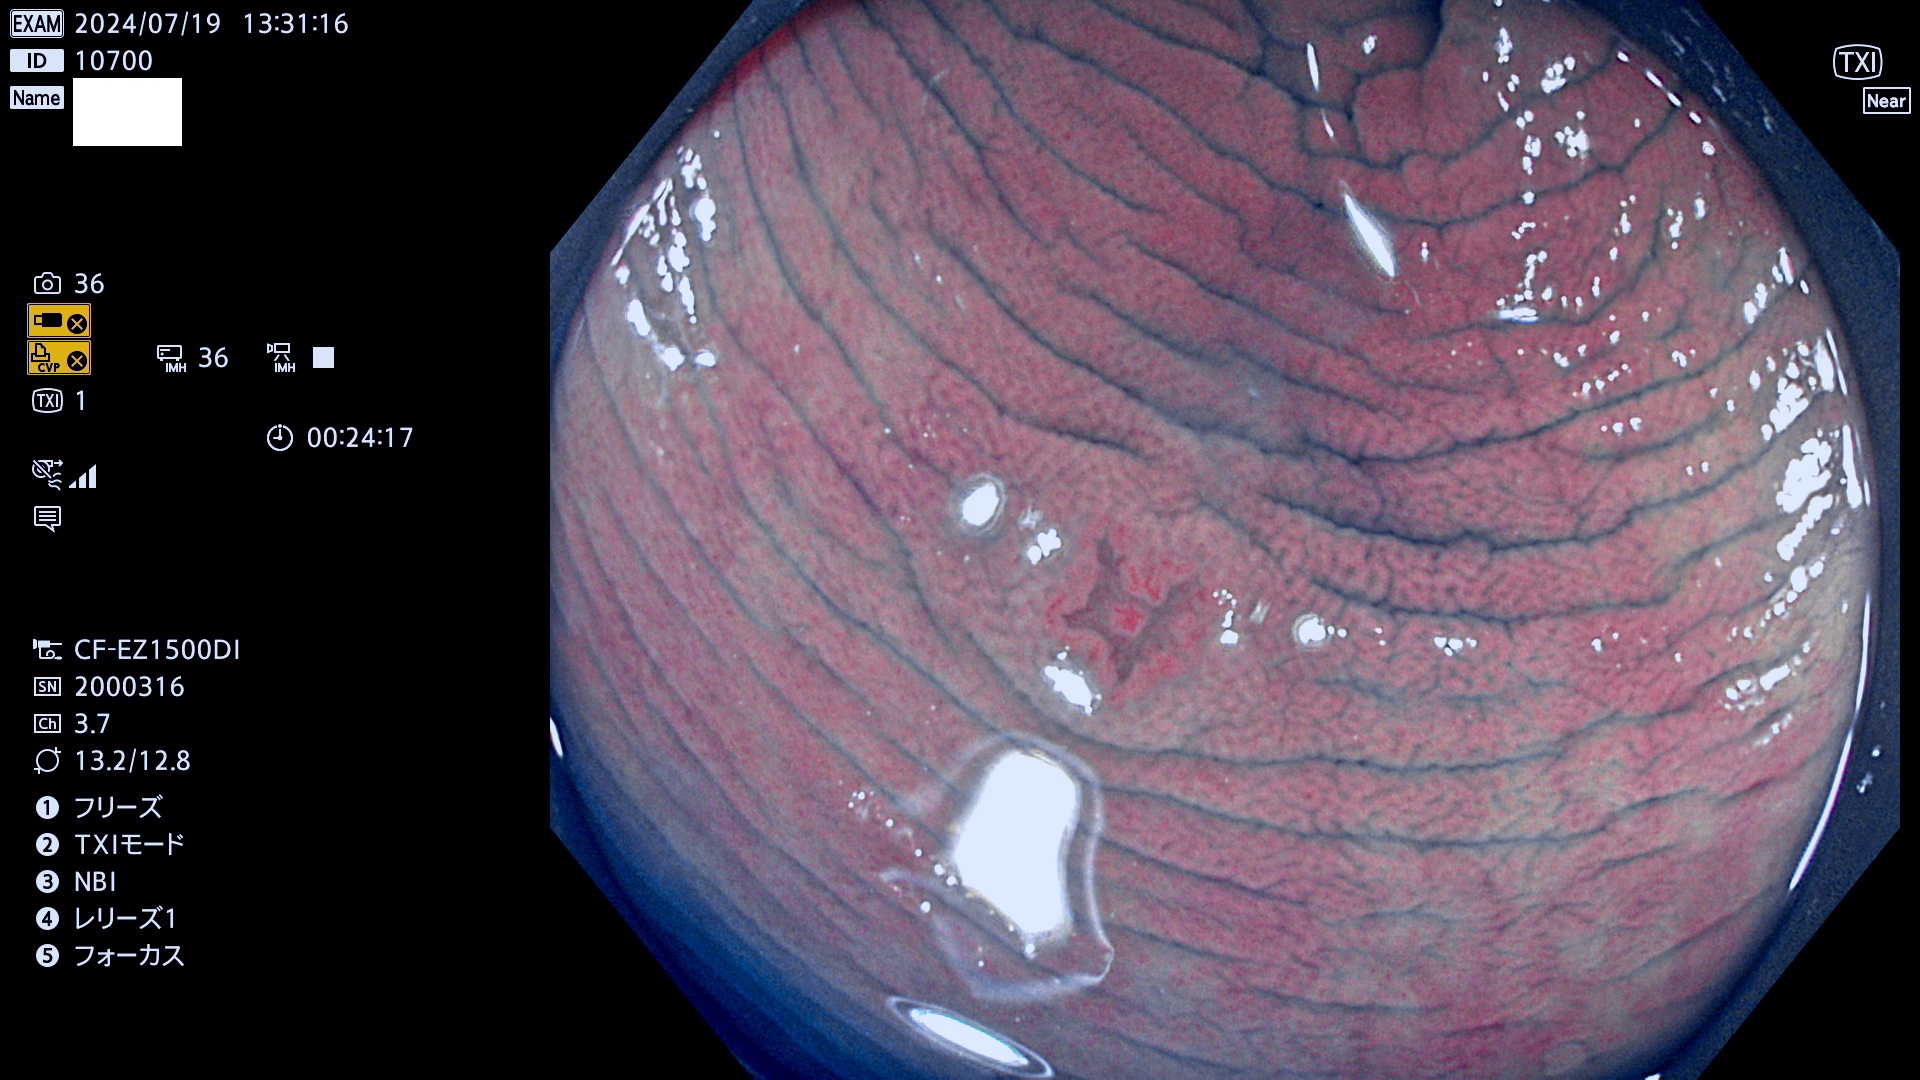

今週のUb、Uc型腺腫

完全に平坦な物をUb、陥凹している物をUcと呼びます。最も発見が難しく危険な病変です。

毎週の検査(木・金・土・日)に発見されたUb、Uc型・腺腫を、その週の日曜の夜にUPし1週間、提示します。

抽出の対象期間 2024年7月18日〜7月21の4日間(25件の検査)6件 (6/25=24%)